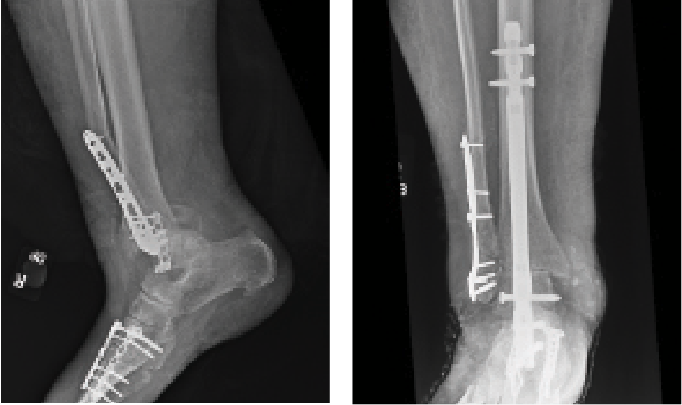

Acute Tibiotalocalcaneal Intramedullary Nailing

Intramedullary tibiotalocalcaneal (TTC) nailing is an established and well-accepted surgical option for degenerative hindfoot and ankle arthritis and for deformities such as Charcot arthropathy. Indications for use have expanded to acute trauma such as ankle and pilon fractures. As a load-sharing implant, this option provides a biomechanically stable construct with minimal soft tissue disruption with the allowance of early weight bearing which is particularly beneficial for the geriatric population. The goal with this fixation construct is stabilization of the operative limb, rather than anatomic reduction.

Georgiannos and colleagues performed a prospective randomized control study comparing TTC arthrodesis versus ORIF in fragility fractures of the elderly. They found equivalent functional outcomes and significantly lower revision rates in the TTC group.16 In contrast, Large and team compared TTC fusion with ORIF in elderly ankle fractures with at least 1 high-risk comorbidity. They found no significant differences in re-operation, infection or union rates between the cohorts.17 While TTC arthrodesis is a viable option for patients, significant complications can arise. Lu and coworkers found high complication rates following TTC arthrodesis in elderly patients with 10% superficial infection, 8% deep infection, 11% implant failure, 11% malunion and 27% all-cause mortality in a high-risk patient cohort with a mean age of 78 years and a diabetes mellitus prevalence rate of 42%.18 Again, a holistic approach should be taken to geriatric patient care, and acute hindfoot intramedullary nailing may best be served for low demand patients with significant comorbidities. Srinath and team developed a framework for choosing hindfoot nailing over standard open reduction internal fixation in the geriatric population. They determined hindfoot nailing is most reasonable in patients with cognitive impairment, uncontrolled diabetes, ASA >2, soft tissue compromise surrounding the ankle, and declining independent mobility.19